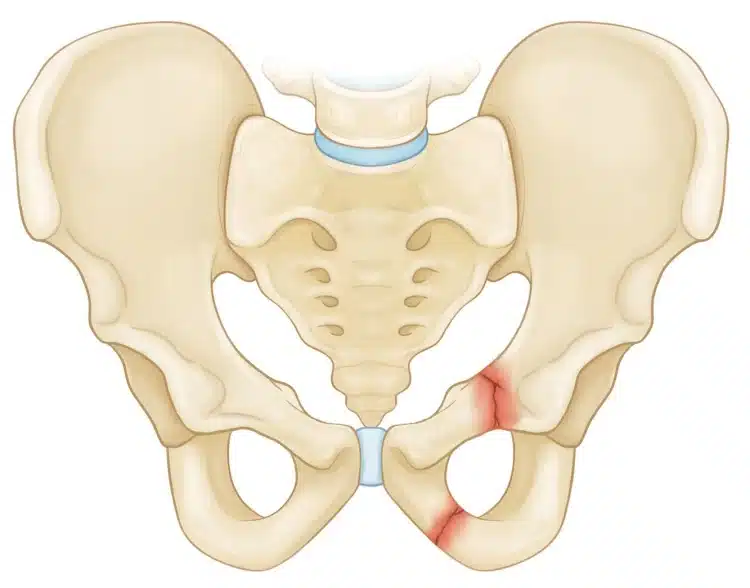

شرخ الحوض البسيط يكون نوع خفيف من الإصابات التي قد يتعرض لها الفرد والتي يمكن التعامل معها بطريقة جيدة والشفاء خلال وقت قصير، ويسمى أيضاً كسر الحوض الثابت والذي يعتبر من أكثر أنواع الكسور التي تحدث بشكل أكبر بين الأفراد، وهذا النوع من الكسور تكون العظام فيه مصطفة في مكانها ويكون الكسر على الأغلب في عظمة واحدة فقط.

ما هي طرق تشخيص شرخ مفصل الحوض؟

ينتج عن كسر في مفصل الحوض ألم شديد يمنع المريض من تحريك مفصل الورك بشكل طبيعي، في حالات الكسر الحاد تترافق الإصابة مع تلف في أحد الأعضاء الداخلية أو تمزق في الأوعية الدموية، مما يؤدي إلى نزيف داخلي قد يقلل من تدفق الدم في الجسم.